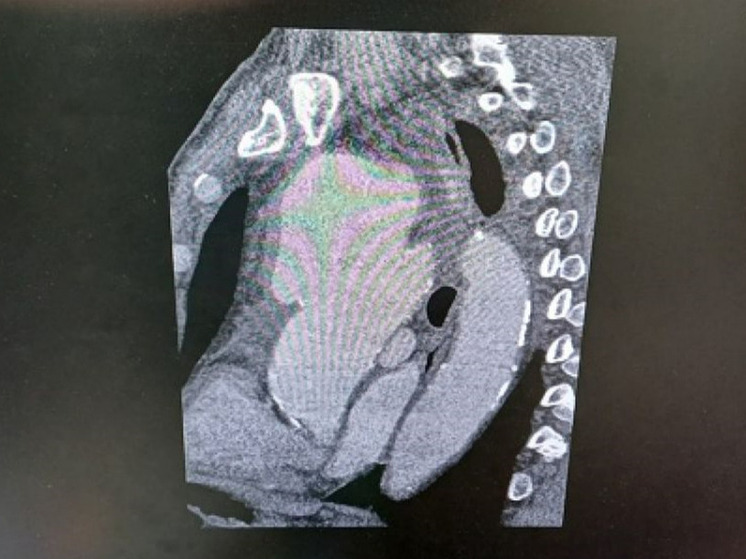

Фото: пресс-служба министерства здравоохранения Рязанской области

Дополнительные исследования подтвердили наличие гигантской аневризмы размером 9 на 9 сантиметров, которая сдавливала соседние органы и ткани. Как отметил заведующий отделением №5 Рязанского кардиодиспансера Сергей Загородный, такие случаи крайне редки, и разрыв аневризмы может привести к летальному исходу.